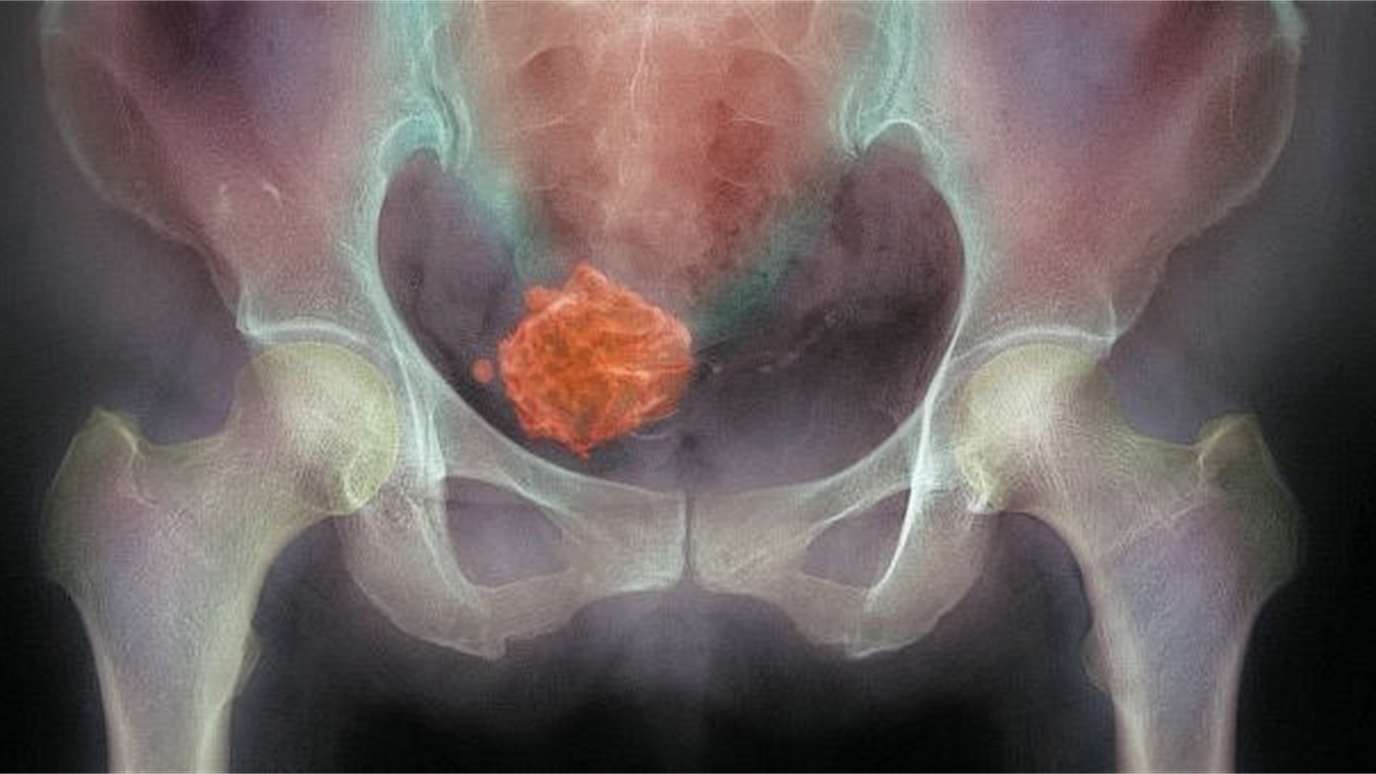

„Máte myom.“

Dvě slova. A svět se zastavil.

Něco tam roste. Něco, co tam nemá být. Něco cizího.

Cítila jsem se obsazená. Jako by se do mého těla nastěhoval někdo, koho jsem nezvala.

Uvědomila jsem si, že myom zabíral mnohem víc místa v mé hlavě než v těle.